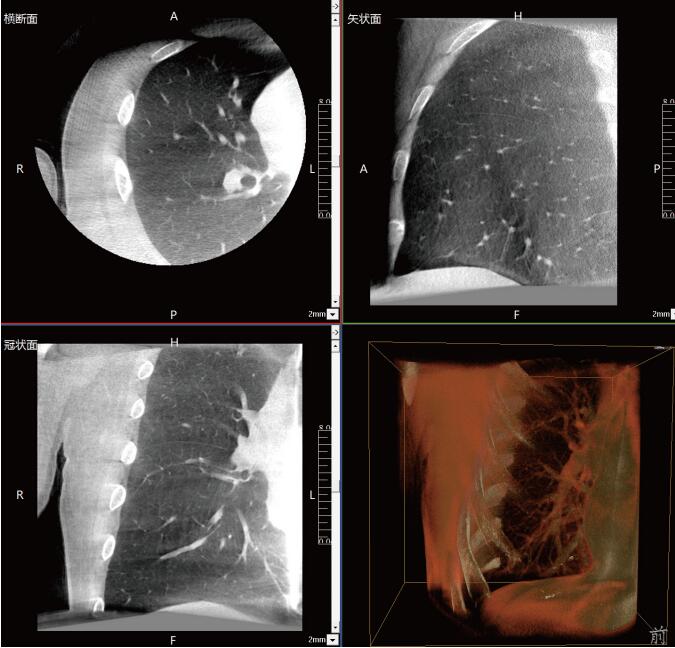

一站式“術(shù)中CT”,肺部診斷+治療新選擇

滿足肺結(jié)節(jié)活檢、肺結(jié)節(jié)切除、肺結(jié)節(jié)消融治療等各類術(shù)式的術(shù)中影像要求:

常規(guī)流程下需要術(shù)前CT室內(nèi)的引導(dǎo)定位,再轉(zhuǎn)入手術(shù)室進(jìn)行胸腔鏡手術(shù),在轉(zhuǎn)運(yùn)過(guò)程中有氣胸、肺出血和導(dǎo)針脫落的風(fēng)險(xiǎn)。使用大功率平板三維C形臂PLX C7600,可在手術(shù)室內(nèi)一站式完成肺部三維影像重建,在穩(wěn)定呼吸的條件下,亞亳米級(jí)定位肺結(jié)節(jié)位置,有效規(guī)避穿刺路徑附近的血管、氣管等重要解剖結(jié)構(gòu),術(shù)中確保穿刺安全有效。同時(shí)可大幅降低輻射劑量,減少射線對(duì)醫(yī)患的傷害。